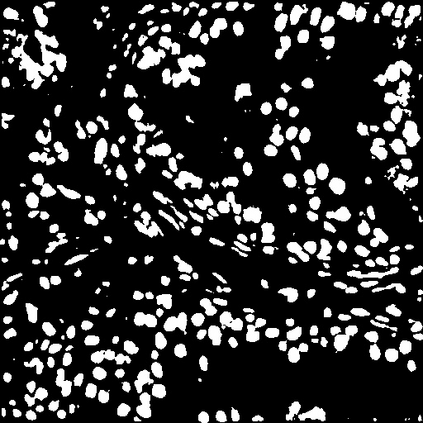

Due to the limitation of available labeled data, medical image segmentation is a challenging task for deep learning. Traditional data augmentation techniques have been shown to improve segmentation network performances by optimizing the usage of few training examples. However, current augmentation approaches for segmentation do not tackle the strong texture bias of convolutional neural networks, observed in several studies. This work shows on the MoNuSeg dataset that style augmentation, which is already used in classification tasks, helps reducing texture over-fitting and improves segmentation performance.

翻译:由于现有标签数据有限,医学图像分割是深层学习的一项艰巨任务,传统数据增强技术已证明通过优化使用少数培训实例来改善分割网络的性能,但是,目前的分割增强方法没有解决若干研究中观察到的动态神经网络的强烈纹理偏差问题。 这项工作显示在MONUSeg数据集中已经用于分类任务的样式增强,有助于减少纹理的过度装配,改善分割性能。